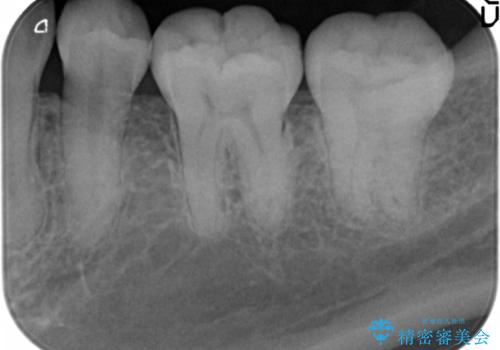

- 奥歯が黒くなっていることを気にされ来院された患者様です。

精査したところ、左下の奥歯にう蝕を認めました。

患者様のご希望により、う蝕を丁寧に除去したのちセラミッククラウンによる補綴治療を行いました。